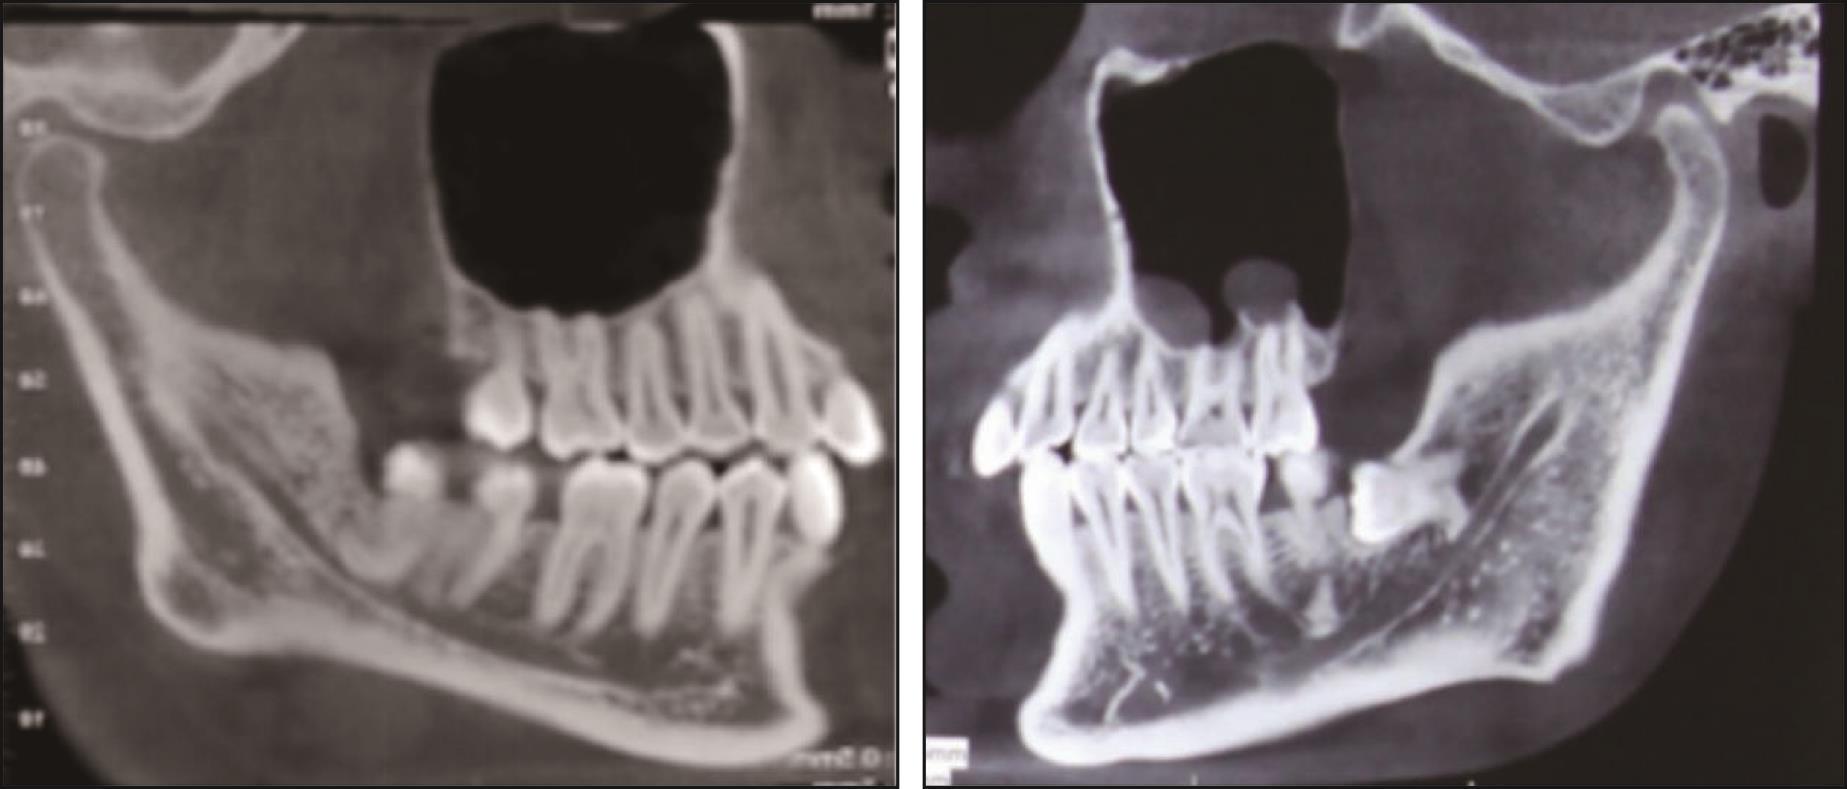

Su Liwen, Zhao Jihong. Management of accidental tooth root displacement into the mandibular canal during tooth extraction[J]. West China Journal of Stomatology, 2025, 43(6): 789-796.

| [16] | 朱天双, 蔡育. 左侧下颌管内断根取出术1例[J]. 口腔医学研究, 2022, 38(11): 1098-1100. |

| Zhu TS, Cai Y. Extraction of fractured root in the left mandibular canal: a case report[J]. J Oral Sci Res, 2022, 38(11): 1098-1100. | |

| [21] | Jiang J, Chen K, Wang E, et al. Endoscopically-assisted extraction of broken roots or fragments within the mandibular canal: a retrospective case series study[J]. BMC Oral Health, 2024, 24(1): 456. |